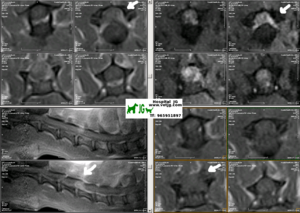

resonancia magnética que localiza y tipifica el problema |